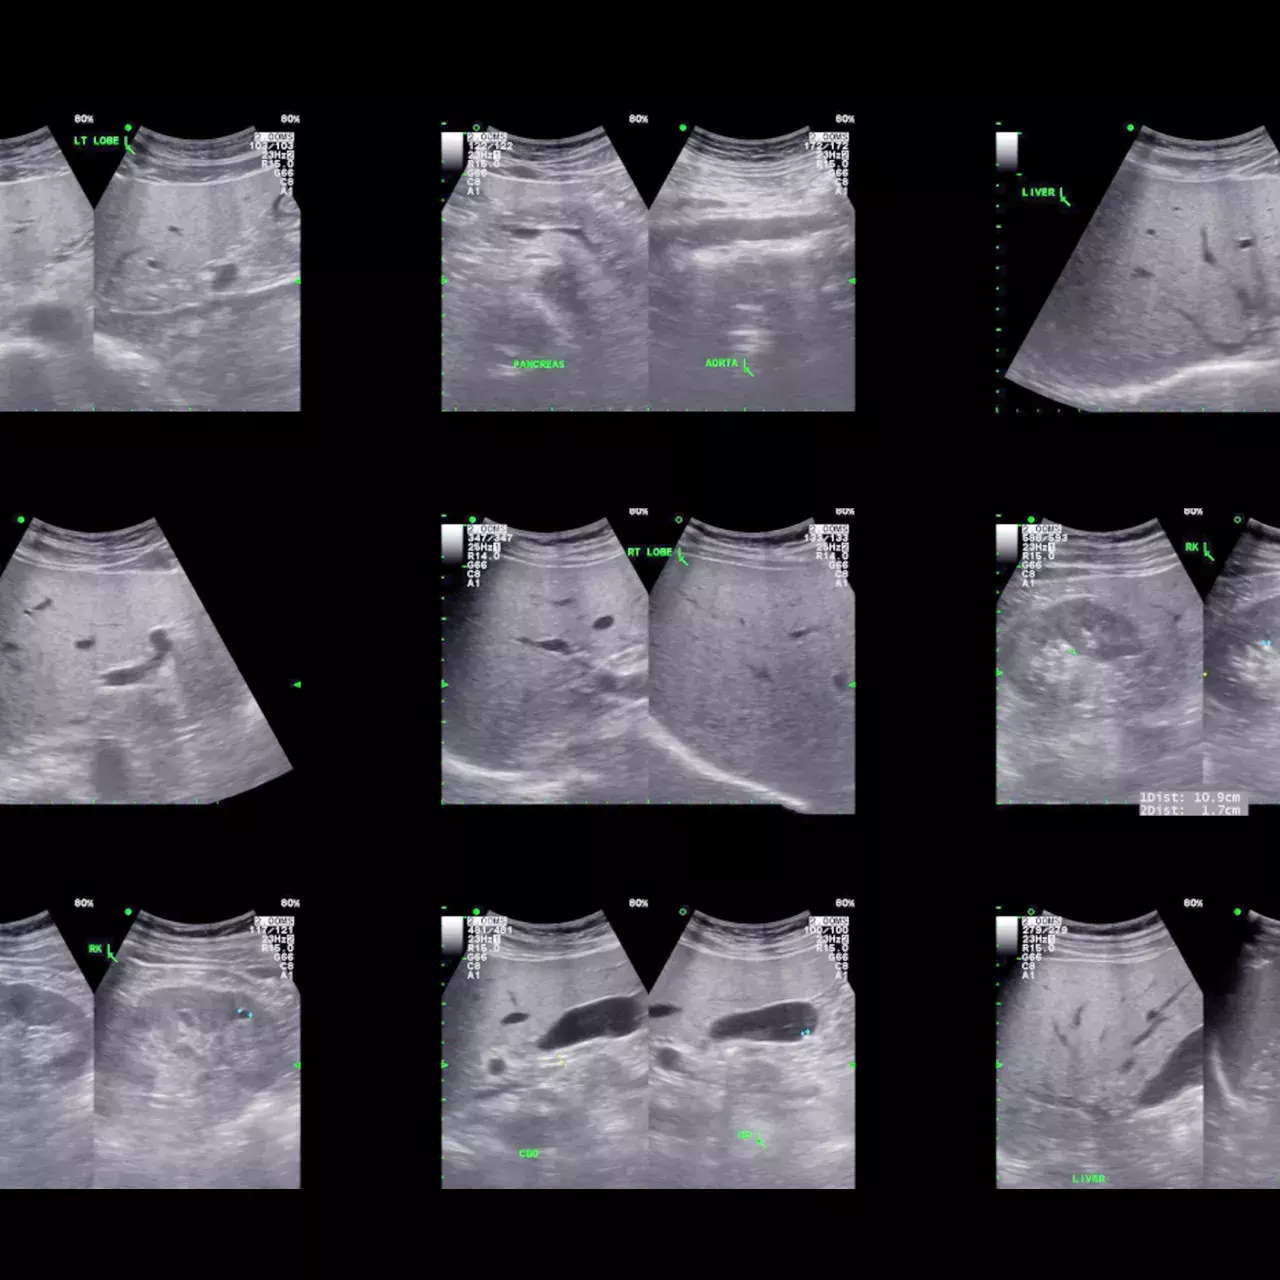

Formation à l’ultrasonographie ciblée

Difficile, voire impossible, de rencontrer une patiente ou un patient qui ne connaisse pas le stéthoscope, l’instrument diagnostic de base que l’on retrouve autour du cou de chaque soignante et soignant ! Mais un nouveau venu a fait son entrée depuis quelques années, c’est l’ultrasonographie ciblée, ou POCUS (Point-of-care ultrasonography), un outil devenu incontournable dans la pratique de la médecine interne générale. Son application requiert une formation rigoureuse, encadrée par des équipes de supervision expérimentées.

Stéthoscope amélioré, le POCUS apporte une précision supplémentaire à l’examen clinique. Non invasive et non irradiante, cette ultrasonographie ciblée est réalisée directement au lit de la ou du patient et est utilisée comme complément à son évaluation. Elle intègre une multitude de données cliniques et des explorations échographiques ciblées, et permet de contrôler des procédures semi-invasives comme les ponctions liquidiennes et vasculaires échoguidées.

Depuis le 1er janvier 2022, dans le cadre de l’obtention du titre FMH de médecine interne générale, il est désormais nécessaire d’obtenir une attestation de formation complémentaire de base en échographie ciblée. La délivrance de cette attestation par la Société suisse d’ultrasons en médecine (SSUM) fait suite à une formation complète qui comprend une initiation théorique, une initiation pratique et la réalisation de 100 à 200 examens échographiques supervisés par une personne experte reconnue par la SSUM.